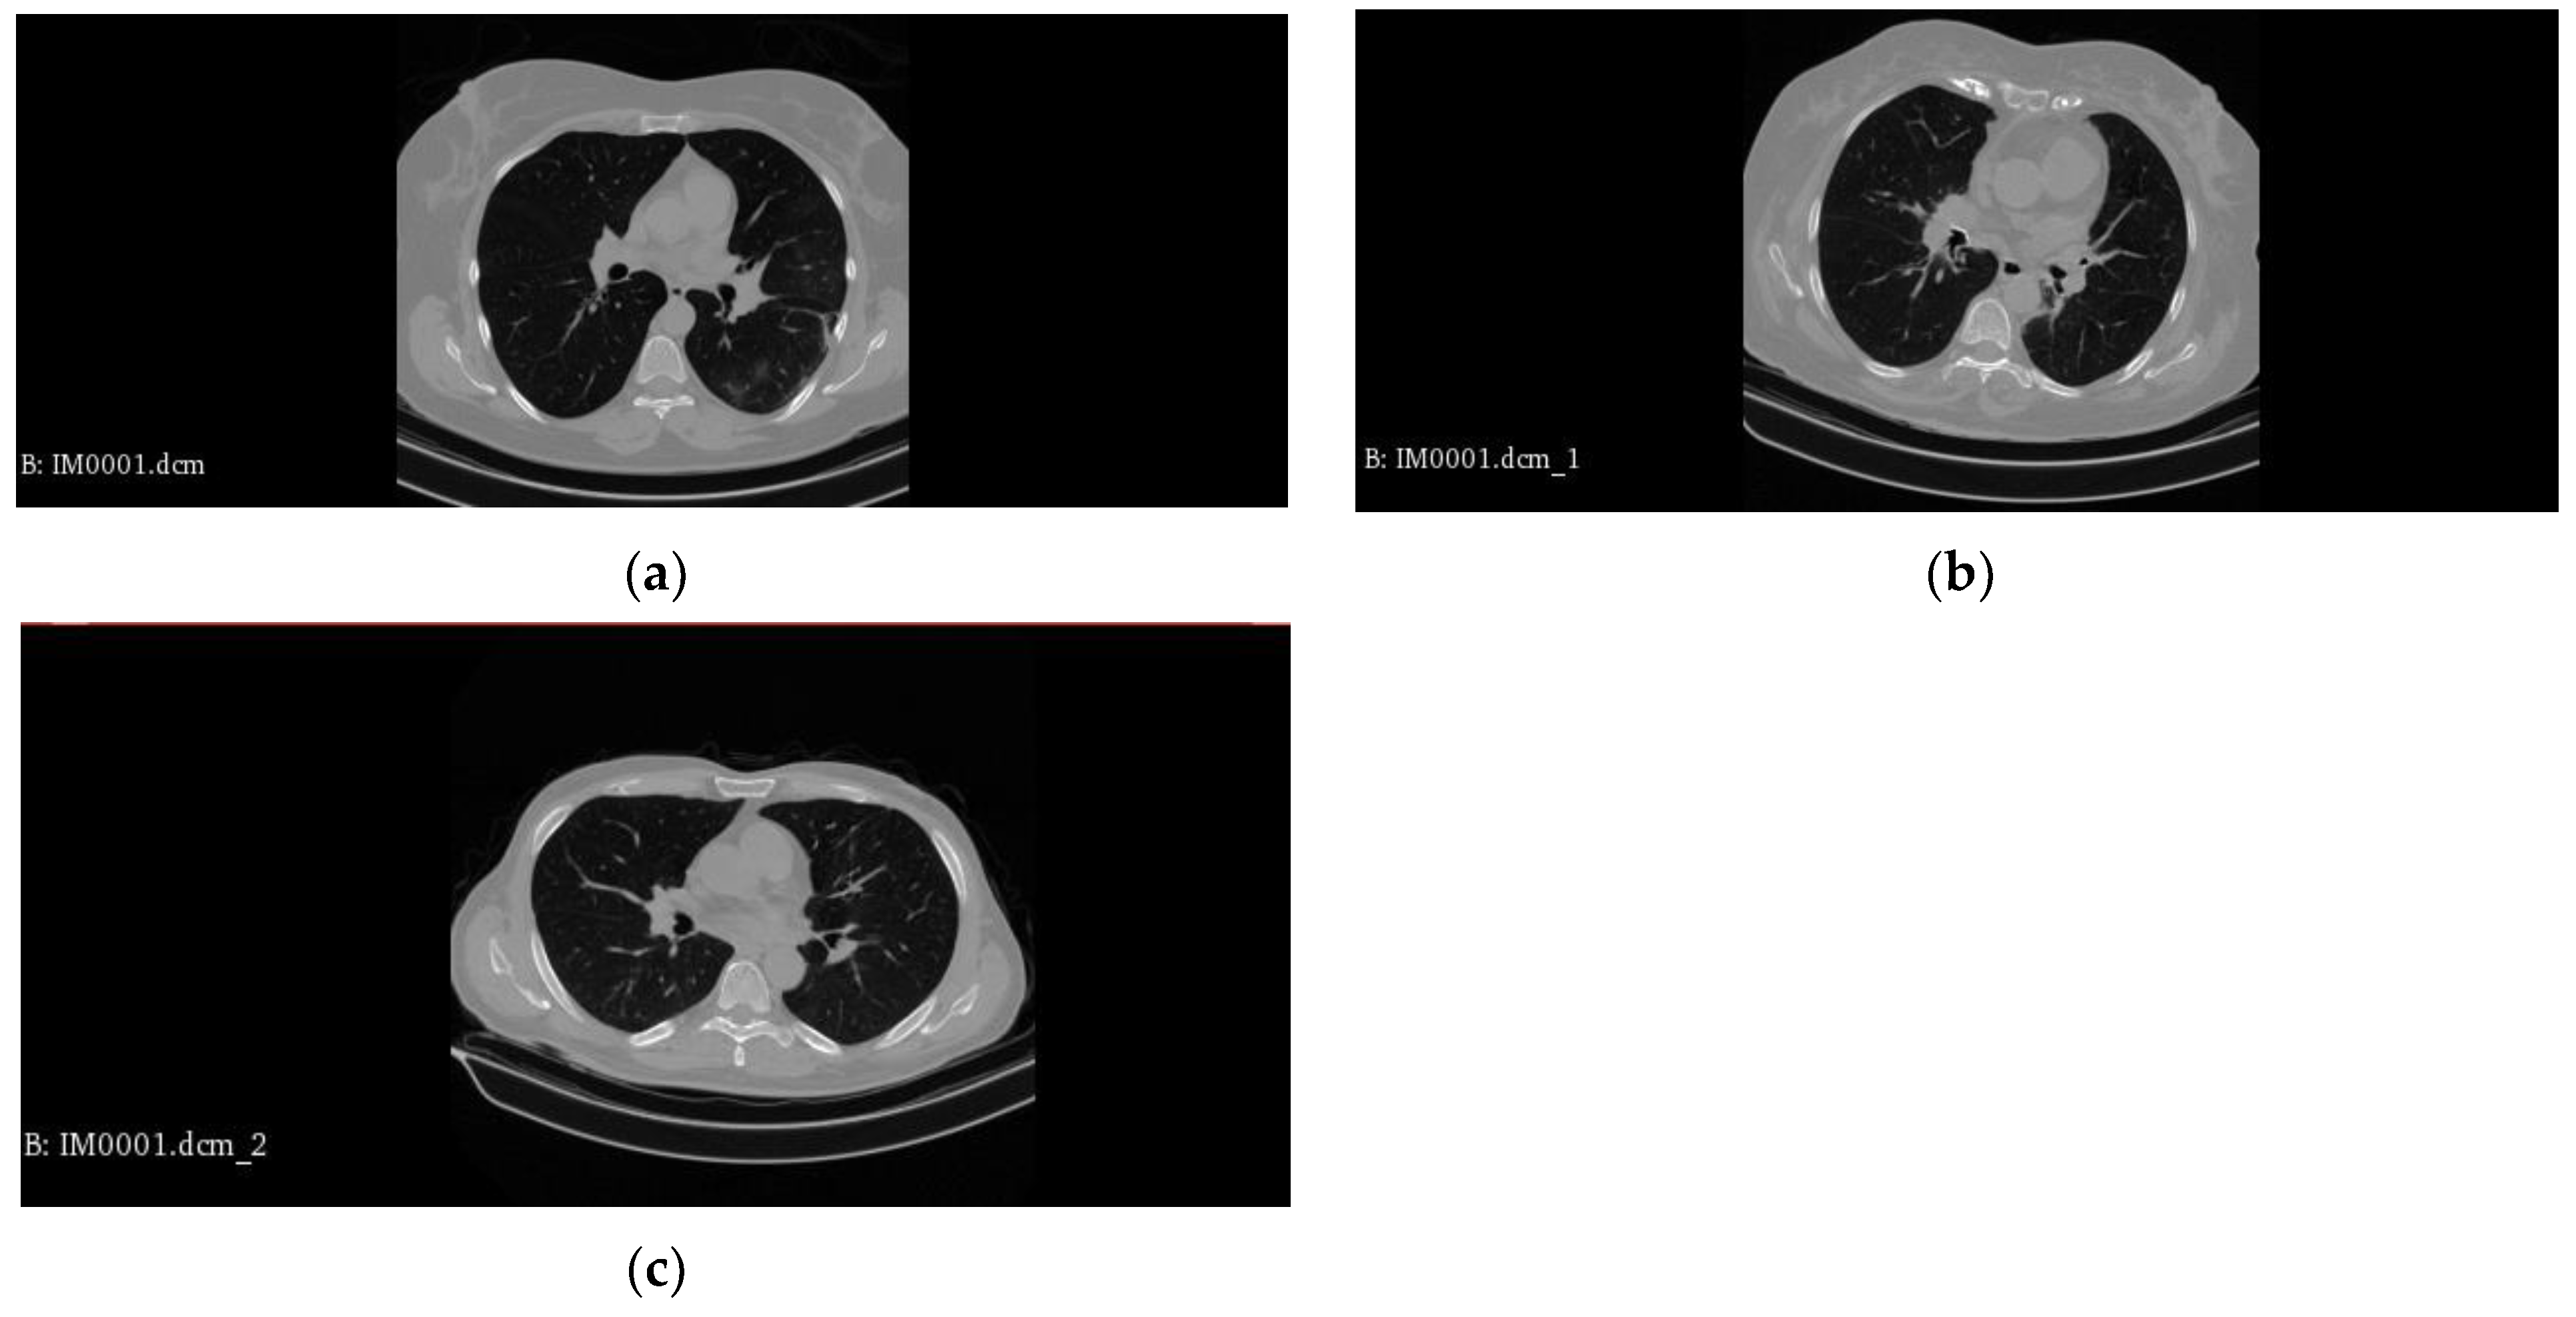

In Figure 1, we can see examples of various classes.

Figure 1.

Representative examples of classes: (a) COVID-19 case; (b) CAP case; (c) Normal case.